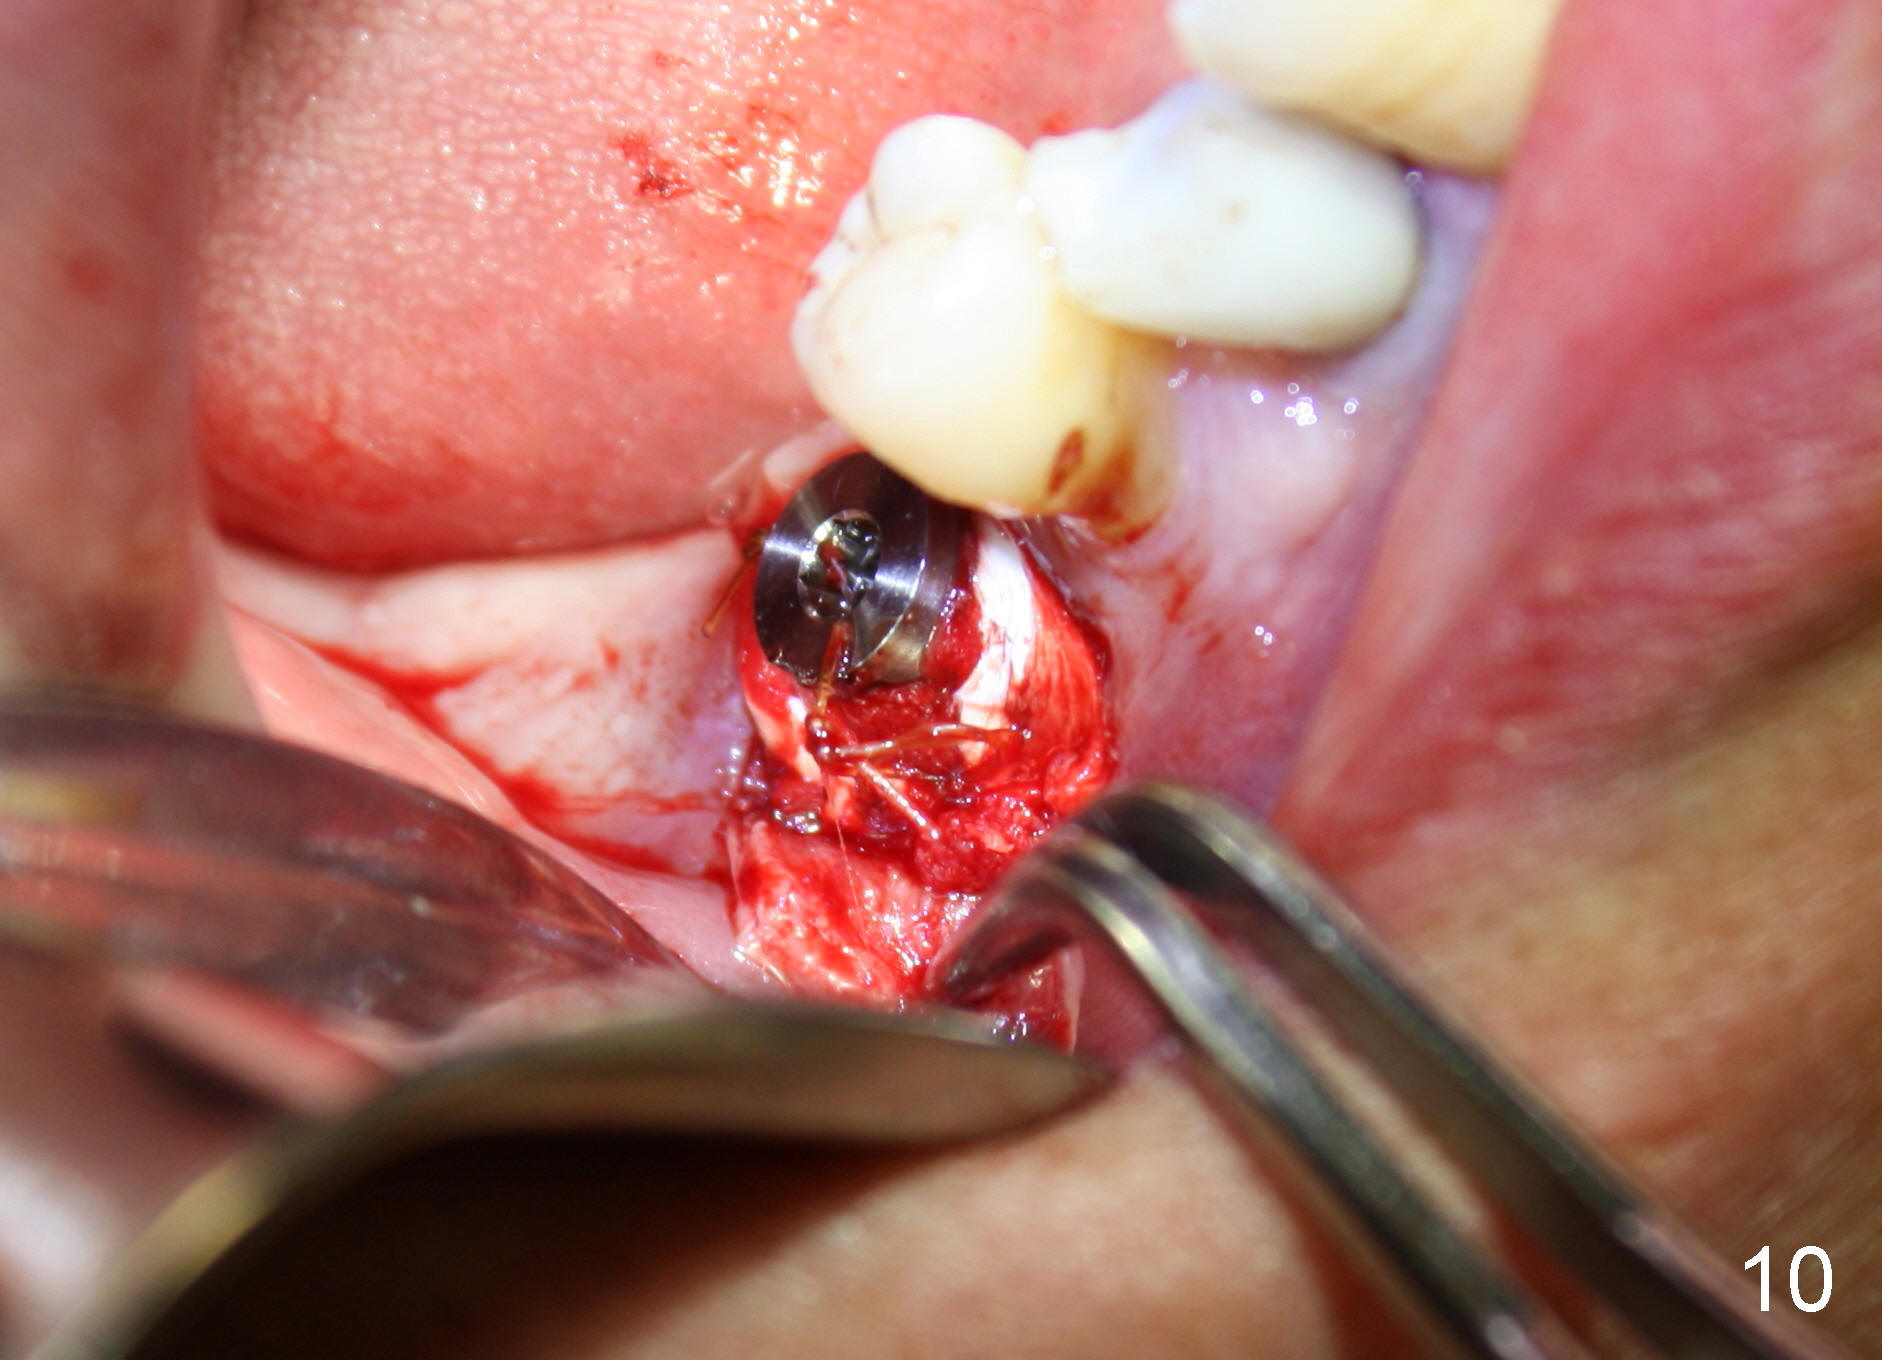

CBCT studies show that a 6x11 mm implant can be safely placed at the site of the tooth #30 (Fig.1 (coronal), 2 (sagittal section). Osteotomy is initiated by 2 mm pilot drill at the depth of 8 mm from the crest (the prospective implant is 3 mm above the crest); X-ray is taken with a parallel pin (Fig.3 P). It appears that there is 12 mm of bone from the crest to the upper border of the inferior alveolar nerve canal. The depth of osteotomy is accordingly adjusted to 11 mm below the crest; osteotomy finishes with insertion of 6x14 mm tap (Fig.4); the patient feels pressure while the tap is being inserted. Following further infiltration with Lidocaine, the depth of the osteotomy is intended to increase in order to bury the implant deeper, because the coronal portion of the buccal plate starts to perforate. The patient feels pain. Finally a 6x14 mm implant is placed ~ 1 mm above the inferior alveolar canal (Fig.5). As mentioned earlier, the rough surface of the implant is exposed buccally (Fig.6 between arrowheads). The nearby buccal plate is decorticated (Fig.7). The autogenous bone harvested during osteotomy (Fig.8) is going to be placed over the exposed portion of the rough surface of the implant (Fig.9); the graft is covered by collagen dressing (Fig.10). The buccal and lingual flaps are approximated with sutures mesial and distal to the implant (Fig.11). To increase the retention of perio dressing, a 4x3 mm abutment is placed.